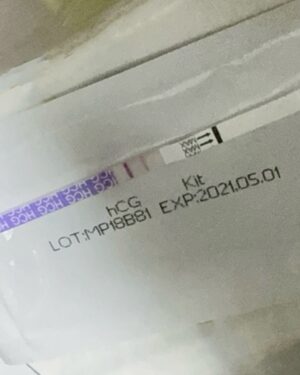

| Profile Photos | |

| https://instagram.com/chantelliu | Most Liked Instagram Photos of Chantel Liu |

View Full List of Most Liked Photos of Chantel Liu | |